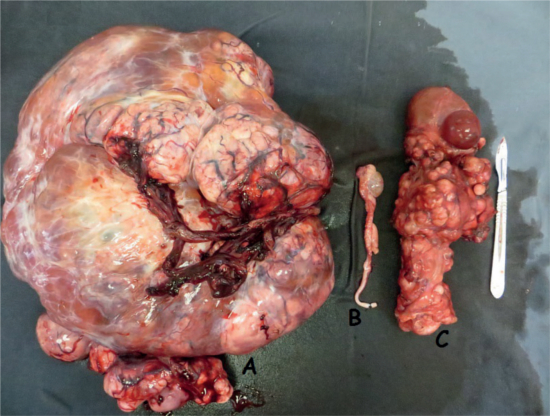

The ultrasound detected a mass occupying most of the cavity, presenting an anechoic formation and different echogenicity structures, moving all the organs of the abdominal cavity. Exploratory laparotomy showed a mass measuring approximately 40 x 40 x 20 cm in the left ectopic testis with metastasis in the left kidney and ureter. Right testicle was stunted. Orchiectomy and left nephrectomy were performed. After histopathological examination, the presence of malignant neoplasia was confirmed on testicles and kidney fragments. The patient was subjected to alternating chemotherapy of doxorubicin and carboplatin, every 21 days doses.

|  Left testis (A); right testis (B); left kidney (C) |